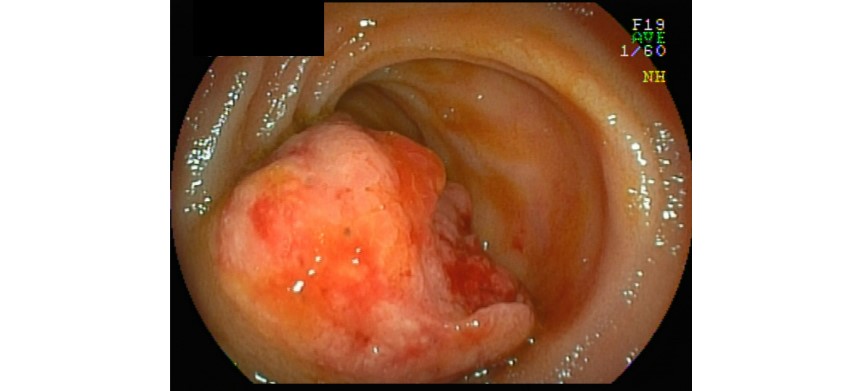

本院腸胃肝膽內科自2025年1月起,提供「膠囊內視鏡檢查」服務,精準抓出病灶,為腸胃消化道的健康嚴格把關,歡迎諮詢腸胃肝膽內科 葉勇呈醫師門診。依據統計,5-10%之腸胃道出血位於小腸,而1-5%的腸胃道腫瘤位於小腸部位,「膠囊內視鏡」的優勢可以觀察到傳統內視鏡檢難以檢查的小腸深部,當經過大腸鏡與胃鏡檢查後仍無法明確診斷出血原因時,可利用它進行檢查與診斷,因此「膠囊內視鏡」具有重要診斷價值。 「膠囊內視鏡檢查」是利用一個約1公分大包覆完整的微型攝影機膠囊,經吞入口中後,經由口腔,進入食道、胃、小腸、大腸,以每秒2張照片以上的影像拍攝速度連續拍攝8小時以上,來獲取消化道內的影像資料;透過胃腸蠕動使其前進,並記錄消化道內部情形,最後經肛門口自然排出。檢查不需要住院且不影響作息,僅需於檢查完畢後交回接收器。